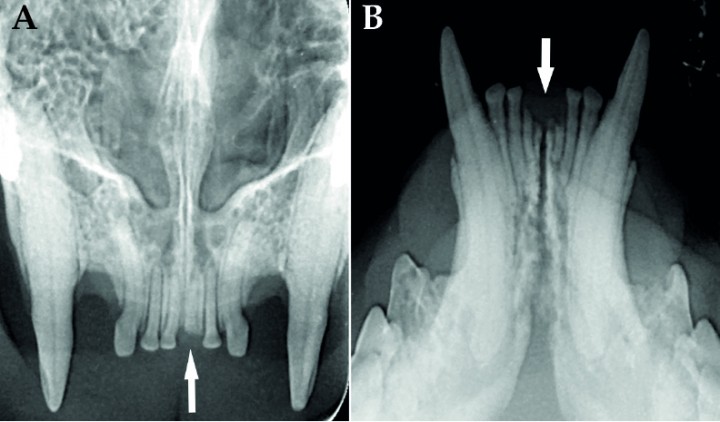

<p>(<strong>A</strong>) Radiografía dental oclusal de los incisivos y caninos maxilares donde se observa el resto radicular consecuencia de fractura dental en 201 (flecha). (<strong>B</strong>) Radiografía dental oclusal de los incisivos y caninos mandibulares donde se observan restos radiculares consecuencia de fracturas dentales en 301 y 401 (flechas).</p>

(A) Radiografía dental oclusal de los incisivos y caninos maxilares donde se observa el resto radicular consecuencia de fractura dental en 201 (flecha). (B) Radiografía dental oclusal de los incisivos y caninos mandibulares donde se observan restos radiculares consecuencia de fracturas dentales en 301 y 401 (flechas).

<p>(<strong>A</strong>) Radiografía dental extraoral de la arcada maxilar derecha. Se observa alteración radiológica compatible con RD de tipo 2 del 106 (flecha). (<strong>B</strong>) Radiografía dental extraoral de la arcada maxilar izquierda. Se observa alteración radiológica compatible con RD de tipo 2 del 206 (flecha).</p>

(A) Radiografía dental extraoral de la arcada maxilar derecha. Se observa alteración radiológica compatible con RD de tipo 2 del 106 (flecha). (B) Radiografía dental extraoral de la arcada maxilar izquierda. Se observa alteración radiológica compatible con RD de tipo 2 del 206 (flecha).